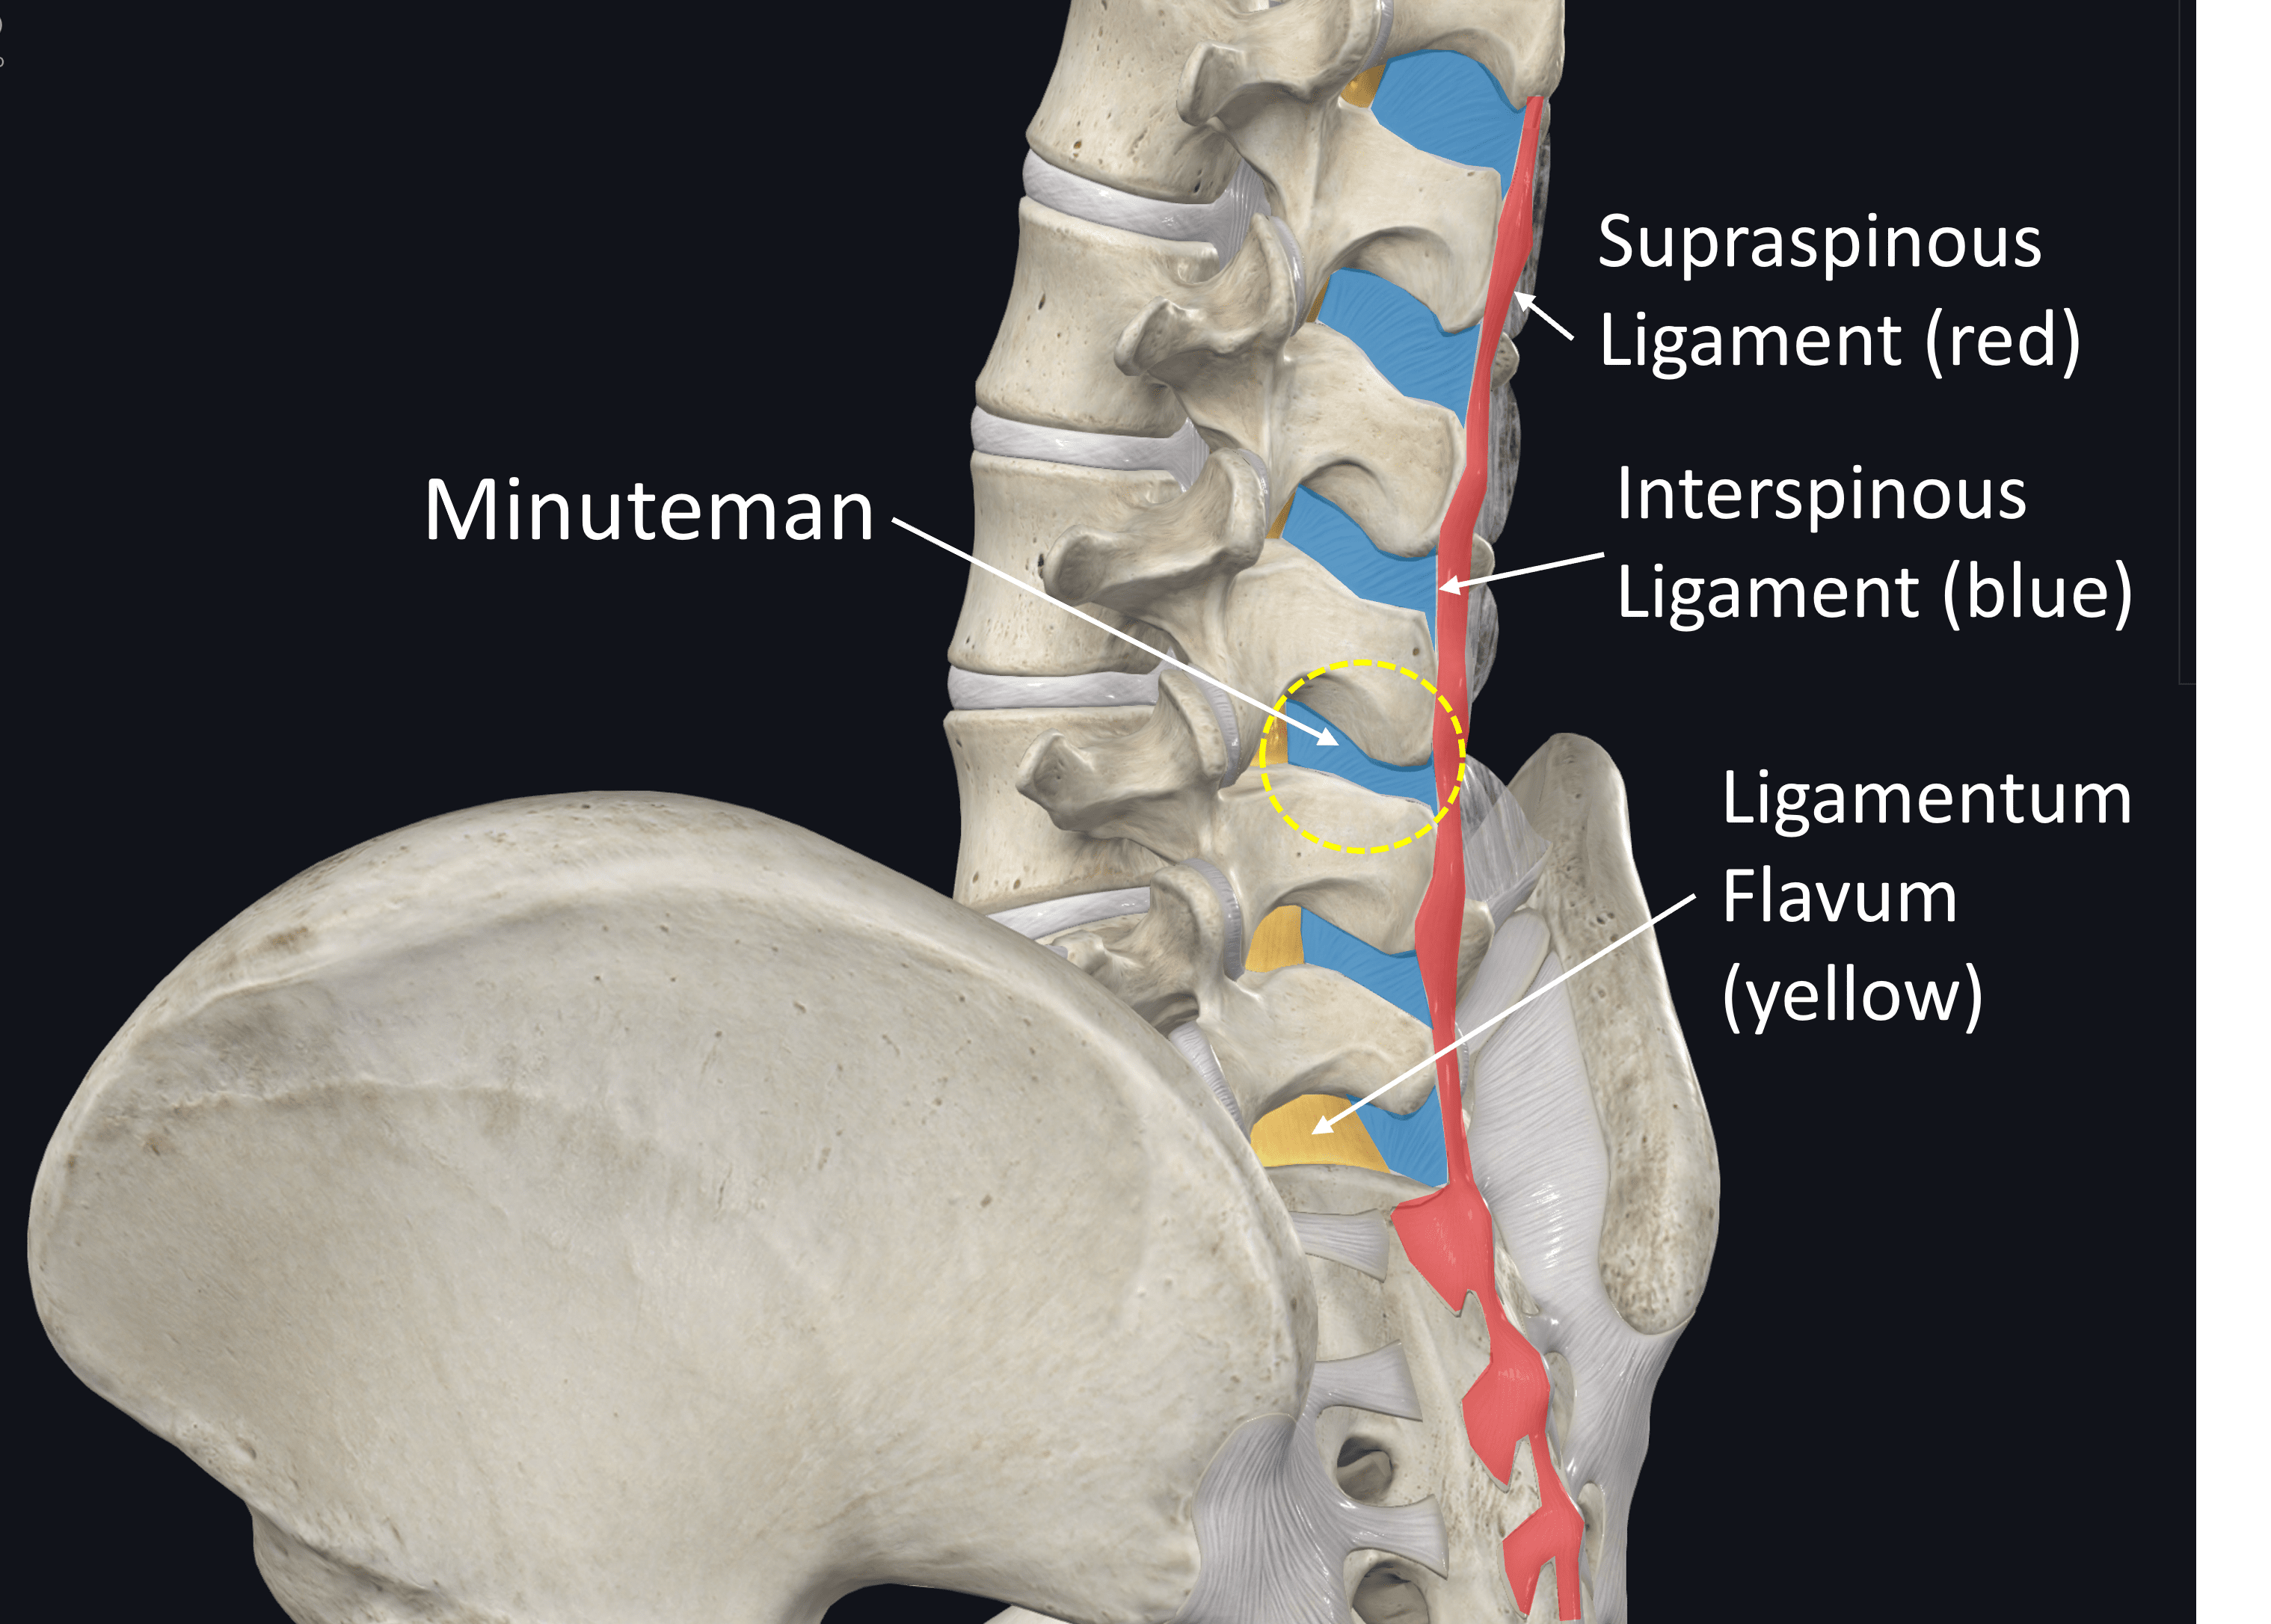

Pure Health - Anatomy 101 - Supraspinous ligament and interspinous ligament 📚 The supraspinous ligament and interspinous ligament work together to limit flexion of the spine by limiting separation of the spinous

DOCS - The interspinous ligament is located between the spinous processes of adjacent vertebrae in the spine. It extends from the base of one spinous process to the apex of the next,